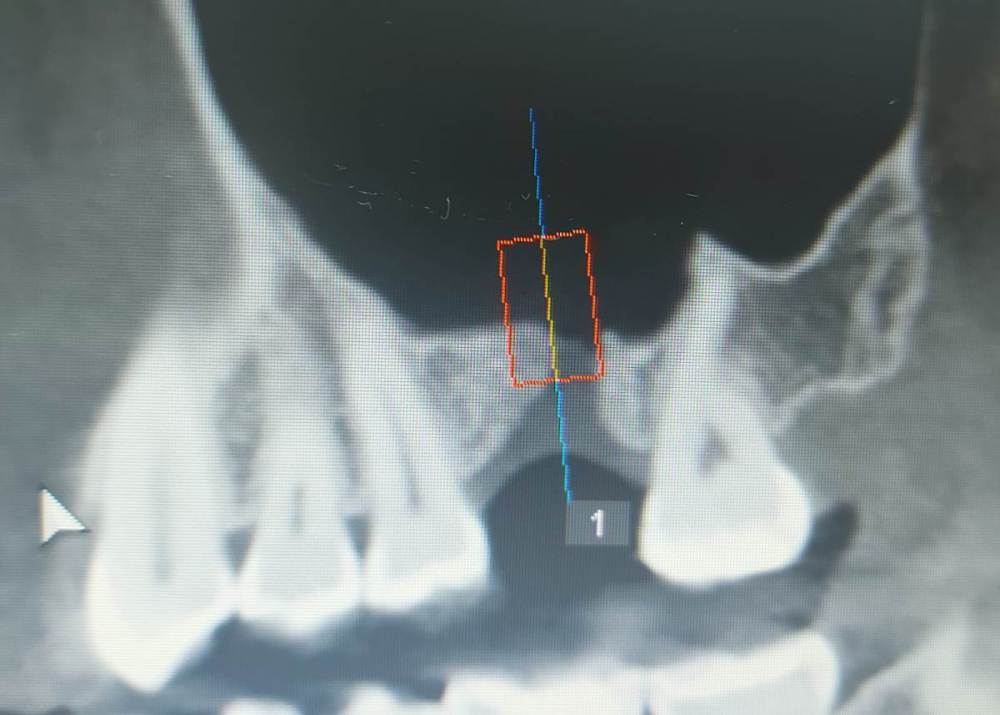

Екатерина А Опубликовано 16 февраля, 2024 Поделиться Опубликовано 16 февраля, 2024 Здравствуйте! Помогите пожалуйста советом. Было удаление 16 зуба с перфорацией пазухи, через месяц была радикальная гайморотомия с пластикой ороантрального свища. Прошло 5 месяцев, сделала КТ прицельное для имплантации зуба, столкнулись с отсутствием кости. Возможен ли синус-лифтинг в моей ситуации? Или что возможно сделать? Почему кость не срослась? Ссылка на комментарий

Irouil Опубликовано 17 февраля, 2024 Поделиться Опубликовано 17 февраля, 2024 Пазух у носа много, а на этом видны только гайморовы и те - частично Надо провести костную пластику этого сегмента альвеолярного гребня, через 4-9 месяцев (в зависимости от используемого метода) имплантация, судьбу соседнего зуба должен решать эндодонт (стоматолог терапевт, который лечит каналы), а не имплантолог Ссылка на комментарий

Екатерина А Опубликовано 18 февраля, 2024 Автор Поделиться Опубликовано 18 февраля, 2024 @Irouil спасибо большое! Костная пластика - это синус-лифтинг в моем случае или что-то другое? Тоже говорят не показан из-за прошлой перфорации при удалении зуба и ороантрального сообщения, что возможно мембрана разойдется по шву. Подскажите, пожалуйста, в каком случае правильно будет? Была уже у нескольких имплантологов Ссылка на комментарий

Irouil Опубликовано 18 февраля, 2024 Поделиться Опубликовано 18 февраля, 2024 @Екатерина А синус-лифтинг, но в Вашем случае скорее всего придётся его немного дополнить/усложнить. В любом случае - не рядовой синус-лифтинг. Сначала надо диагностику завершить, то самое КТ черепа, о котором говорил коллега @red_butler выше 1 1 Ссылка на комментарий

АнтонТЛТ Опубликовано 18 февраля, 2024 Поделиться Опубликовано 18 февраля, 2024 Вообще проблем не вижу сделать синус-лифтинг с одномоментной имплантацией при отсутствии воспалительных изменений в пазухе 1 1 Ссылка на комментарий